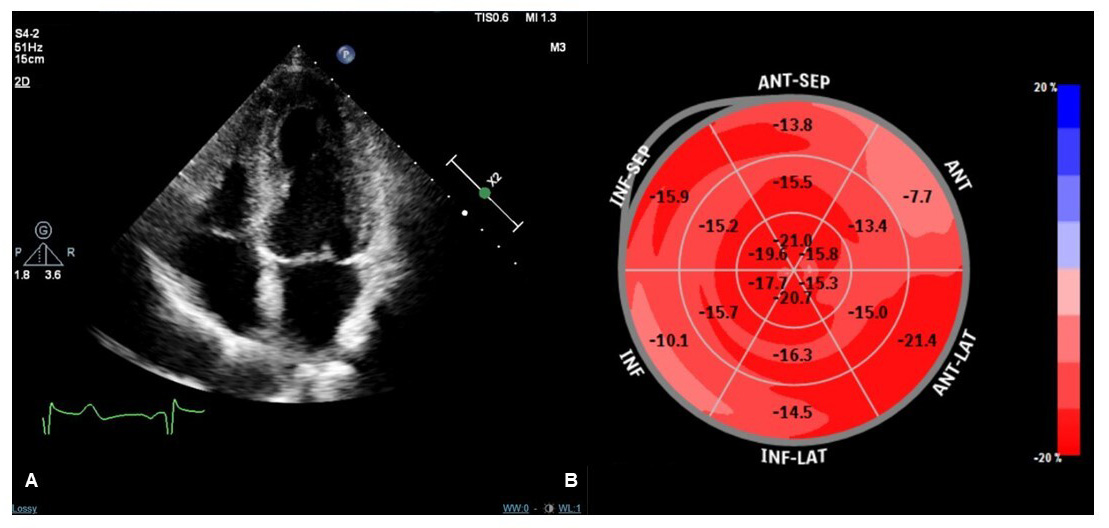

TTE is an essential tool in the follow-up evaluation of patients with TTS. Complete recovery of regional wall motion abnormalities and LVEF must be documented to confirm the diagnosis of TTS. Typically, LVEF fully recovers within a month after the acute event [89], but there are patients with a more rapid versus slower recovery [47, 90]. Nevertheless, other functional LV abnormalities may persist despite LVEF normalization. Novel, advanced echocardiographic techniques may provide an accurate and sensitive detection of these abnormalities during the recovery phase of TTS clinical course. Speckle tracking-TTE (ST-TTE) provides parametric quantification of myocardial chambers deformation and assessment of LV global longitudinal strain (GLS) by ST-TTE may have an important prognostic value. Indeed, within the first few months after TTS hospitalization, LV-GLS has been consistently described to be impaired despite normalization of LVEF [89, 91], and a reduced LV-GLS at 3 months after TTS is associated with both persistent elevation of natriuretic peptides and increased perception of impaired physical exercise capacity [92]. In addition, impairment of LV longitudinal systolic function was observed by ST-TTE even more than one year after the acute event [65]. Further research is needed to confirm whether these alterations of systolic function are a pre-existing factor, rather than a consequence of TTS, or complete recovery is possible at a later stage. In fact, long-term ST-TTE studies provided conflicting results: the complete recovery of systolic function has been described [93], as well as the persistence of disturbances of rotational strain with normalization of GLS [94]. The role of stress echocardiography in TTS follow-up is unclear since studies on this topic are small and conflicting data have been reported. A first case-control study of 22 patients with previous TTS undergoing dobutamine stress echocardiography showed no signs of diastolic or systolic dysfunction during pharmacological stress [95]. A subsequent case–control study comparing 30 patients with previous TTS and persistent symptoms who were referred for exercise echocardiography reported reversible exercise-induced LV contractile dysfunction [96]. The Authors hypothesized that exercise-induced hyperactivation of autonomic nervous system and higher levels of norepinephrine may induce endothelial dysfunction, coronary vasoconstriction, microvascular dysfunction, increased cardiac workload, and direct myocardial toxicity [96]. However the clinical implications of stress-induced LV dysfunction in TTS patients are unclear, and studies with greater cohort and longer follow-up are required to determine whether it is associated with a worse prognosis. Moreover, many case reports and a recent study reported of TTS triggered by dobutamine stress echocardiography [97, 98, 99]. Thus, the role of exercise echocardiography in TTS follow-up remains to be defined, while the use of dobutamine stress should be avoided due to the non-trivial risk of recurrence. At the present time, standard TTE appears sufficient to confirm TTS diagnosis and it is essential in the first outpatient examination both to document complete LV recovery and to evaluate the diastolic function which provides useful prognostic indications as well [90]. More advanced techniques, such as ST-TTE, could be useful in persistently symptomatic patients in order to evaluate possible abnormalities in LV systolic function [92]. Fig. 2 shows normalization of LV-GLS in a TTS patient one month after the acute event.

Fig. 2.Transthoracic echocardiography (TTE) imaging of a TTS patient performed one month after the acute event. Apical four-chamber view during systole showing no regional kinetic abnormalities (A). Speckle tracking-TTE (ST-TTE) showing a normal value of LV global longitudinal strain without significant regional abnormalities of myocardial chamber deformation (B).